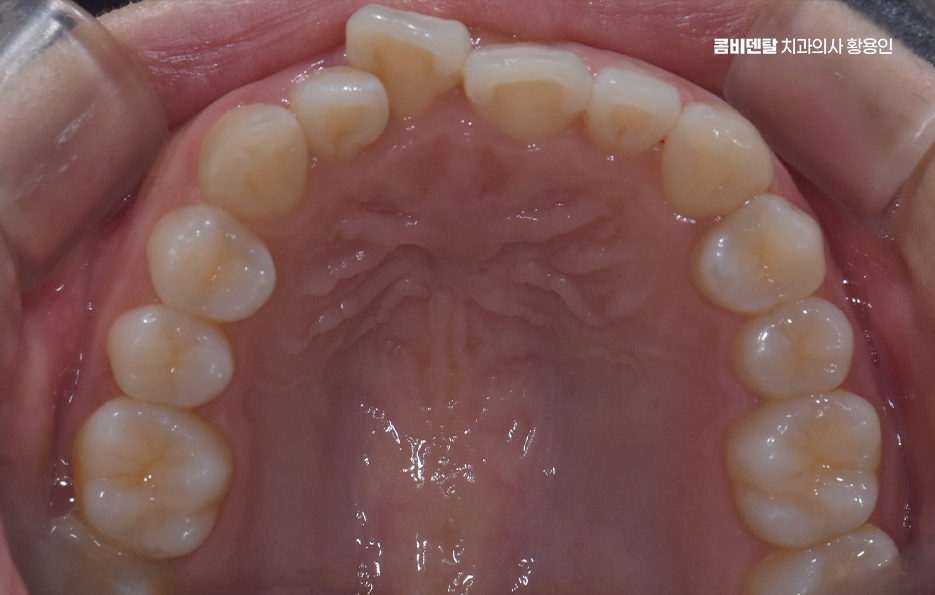

치아 교정을 할 때 통증을 느끼는 정도는 교정 치료의 방식이나 사용되는 장치, 발치 여부 등에 따라서도 차이가 있어요. 치아 교정은 치아를 이동시키면서 새로운 위치에 자리 잡도록 하는 과정이기 때문에 일정한 압력이 가해지면서 불편함이나 통증이 생길 수 있지만 이러한 통증은 시간이 지나면서 점차 완화되기 때문에 너무 걱정할 필요는 없으며 교정 치료를 받는 동안 치아교정 통증 줄이는 방법 또한 있기 때문에, 교정 과정을 좀 더 편안하게 진행할 수 있도록 여러 가지 방법을 활용하신다면 좋을 거예요

교정 통증이 발생하는 가장 큰 이유는 치아가 이동하면서 주변 조직과 신경이 자극을 받기 때문으로 치아는 잇몸 뼈와 치주 인대에 의해 고정되어 있는데, 교정 장치를 부착하면 치아가 천천히 이동하면서 치주인대에 압박이 가해지고, 이로인해 혈류량이 감소하면서 신경을 자극하는 대사물질이 생성되어 통증이 발생하고, 이 과정에서 압박되는 쪽 뼈가 녹고, 반대쪽 여유공간에서 뼈가 재 형성되면서 통증이 발생하는 거예요.

일반적으로 발치를 동반하는 교정의 경우, 통증이 좀더 더 심할 수 있는데 발치를 하면 인접한 치아가 그 빈 공간을 메우기 위해 이동하고 이 과정에서 기존보다 더 강한 힘이 가해지면서 불편함이 커질 수 있어요.

교정 장치의 종류에 따라서도 통증의 정도가 다를 수 있는데 일반적인 금속 브라켓을 사용하는 경우, 초기에는 금속이 입 안쪽에 닿으면서 불편함을 느낄 수 있어요. 특히 교정 와이어를 조절할 때마다 일정한 힘이 가해지기 때문에 몇 일 동안은 씹는 것이 불편할 수도 있지만 반면, 클리피씨 같은 자가 결찰형 브라켓을 사용하는 경우, 마찰력이 줄어들면서 치아 이동 속도가 상대적으로 빠르고, 통증이 덜하다고 느낄 수 있어요. 또한 투명 교정이나 인비절라인 같은 경우에는 탈착이 가능하고 교정기로 인한 통증이 일반교정에 비해 상대적으로 덜한 편이라는 특징이 있어요